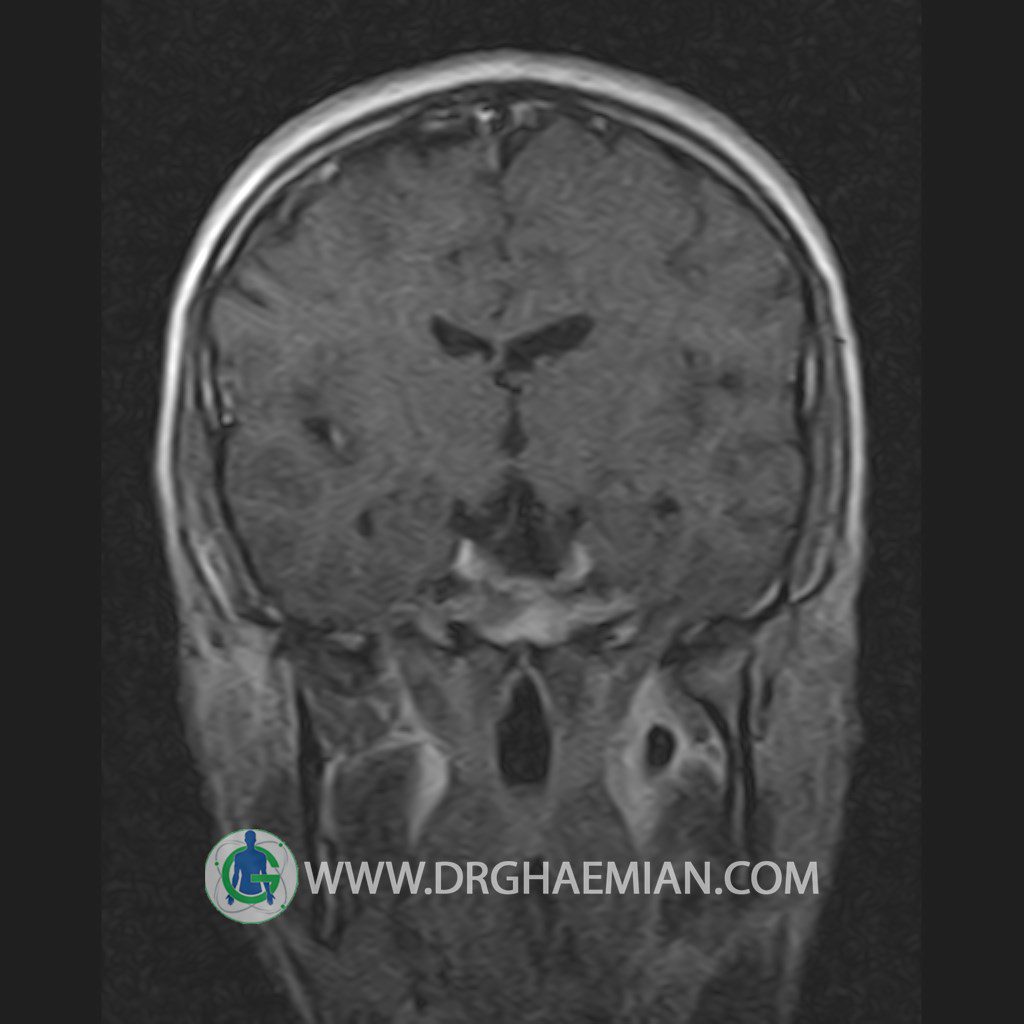

پزشکان اغلب از تصویربرداری ام آر آی برای تشخیص و درمان عارضه های پزشکی که فقط با استفاده از اشعه ایکس یا میدان مغناطیسی و امواج رادیویی قابل مشاهده است، استفاده می کنند. دستگاه ام آر آی تصاویر دقیق از ساختار های داخلی بدن ایجاد می کند. در این کیس یک میکروآدنوم در هیپوفیز بیمار مشاهده می شود.

HYPOPHYSIS MRI

(with and without contrast)

Technique: Axial , coronal T1 , Axial , coronal , sagittal T2 , Axial, coronal T1 post Gd & 64 dynamic thin coronal slices.

REPORT :

The infundibulum is centered and of normal size .

The optic chiasm and suprasellar spaces appear normal .

The cavernous sinus and imaged portions of the internal carotid artery and carotid siphon are unremarkable .

Evaluable portions of the neurocranium show no abnormalities .

The sphenoid sinus is clear and pneumatized .

Imaging of the hypothalamus after contrast medium administration was normal.

– Small hypoenhancing mass lesion ( 3 x 4 mm ) in posterior of pituitary stalk suggestive for micro adenoma

– Mucosal thickening in ethmoid & maxillary sinuses

is seen